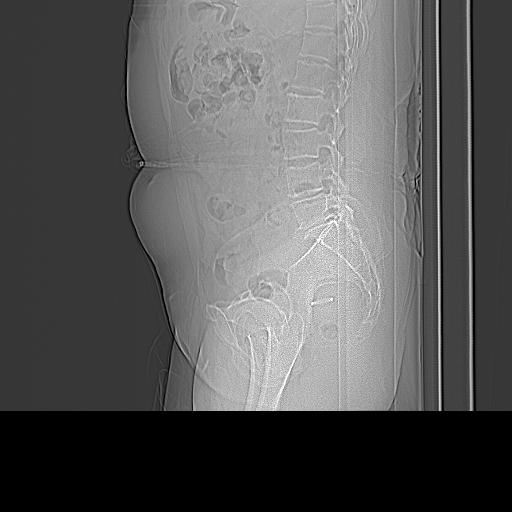

患者;女性;左下肢疼痛。

l5s1显示椎间盘突出,椎体边缘骨质增生,双侧黄韧带钙化。(请上传骨窗)

l45未扫描,估计可能有椎间盘突出。

l5s1显示椎间盘突出,椎体边缘骨质增生,双侧黄韧带钙化 ,两侧椎小关节肥大,关节面硬化,关节间隙变窄,提示:椎小关节综合症

双侧的侧隐窝有狭窄。

我认为应该考虑为:l5s1椎间盘膨出,余(椎小关节退变、黄韧带钙化、椎间孔狭窄)与各位同行无异议。

l5s1显示椎间盘膨出,突出,椎体边缘骨质增生向后压迫硬膜囊,双侧黄韧带钙化,小关节面综合征

l4-5椎间隙略窄,应该扫描。

l5s1椎间盘向后脱出使脊膜囊受压,椎体边缘骨质增生,双侧黄韧带钙化。l45椎间盘估计亦突出,为何未扫。